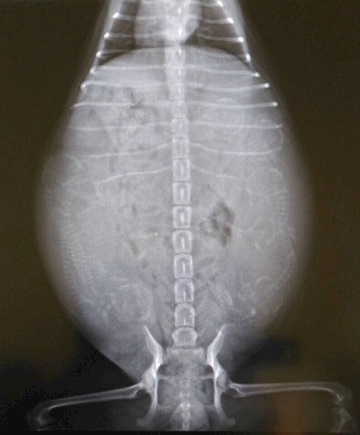

4匹の命が

宿ってるはずが……

6匹います

レントゲン

が頭だよぉ~~

チワワにしては

6匹は多いらしく

難産になり母体も

危険という事で

帝王切開予定……